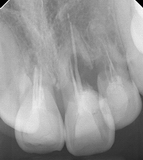

治療前のエックス線

治療前のエックス線

歯根が吸収していて残せない状態でした